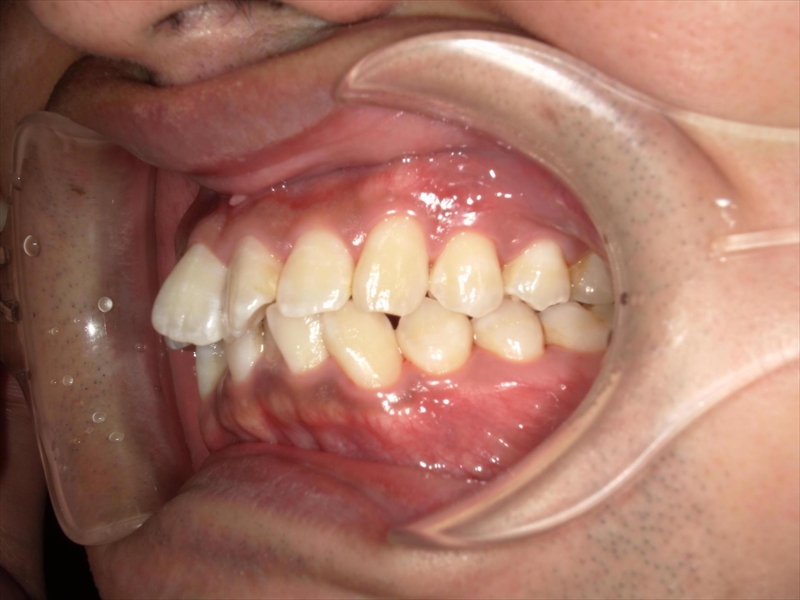

- 上あごの前歯がV字状の出っ歯

- 下あごの前歯もがたついている(叢生)

- 上あごに対して下あごがかなり小さい(過蓋咬合)

前歯のねじれ(V字)と出っ歯を下げるスペースを確保のため、両側1~5番目を0.2~0.5ミリ(計4ミリ)削ることと、奥歯から順に奥へ下げながら外側へ広げる計画を立案しました。

上あご同様、スペース確保のため、両側1~5番目までを各0.5ミリ(計5.5ミリ)削ることと、奥歯から順に奥へ下げながら外側へ広げる計画を立案しました。